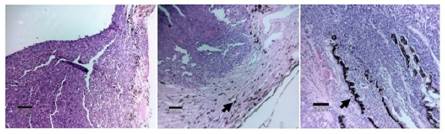

Cortes histopatológicos (Figura 7). Proliferación neoplásica neuroectodérmica, crecimiento infiltrativo organización difusa, en nidos y cordones cortos; células de citoplasma eosinofílico, algunas escasas con gránulos de melanina, pleomorfismo celular leve, anisocitosis moderada; núcleo de cromatina gruesa, pleomorfismo nuclear, cariomegalia moderada y anisocariosis moderados; conteo de 17 figuras mitóticas en 2.37 mm2 (10/hpf), invasión de vasos sanguíneos intratumorales, moderada necrosis e infiltrado mixto multifocal, moderada congestión y edema multifocal.